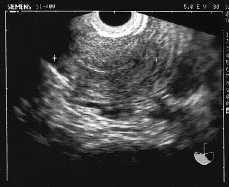

-- OD de 39 * 26 mm con imagen adyacente de saco gestacional con embrión de 3 mm (5,5 semanas) y LF positivo.

-- Diagnóstico compatible con EE en trompa derecha no accidentado en el momento del diagnóstico y OI quístico.

El hallazgo de un EA en estadio precoz (5,5 semanas) ha sido en este caso un hecho fortuito, ya que el diagnóstico temprano de un EA es difícil, pero esencial, dado que la separación de la placenta puede asociarse con una hemorragia fatal(8,9). Por otro lado, la ecografía al principio suele confundir el EA con uno tubárico, como es nuestro caso, pero a medida que evoluciona la gestación se hace más fácil el diagnóstico(10,11).